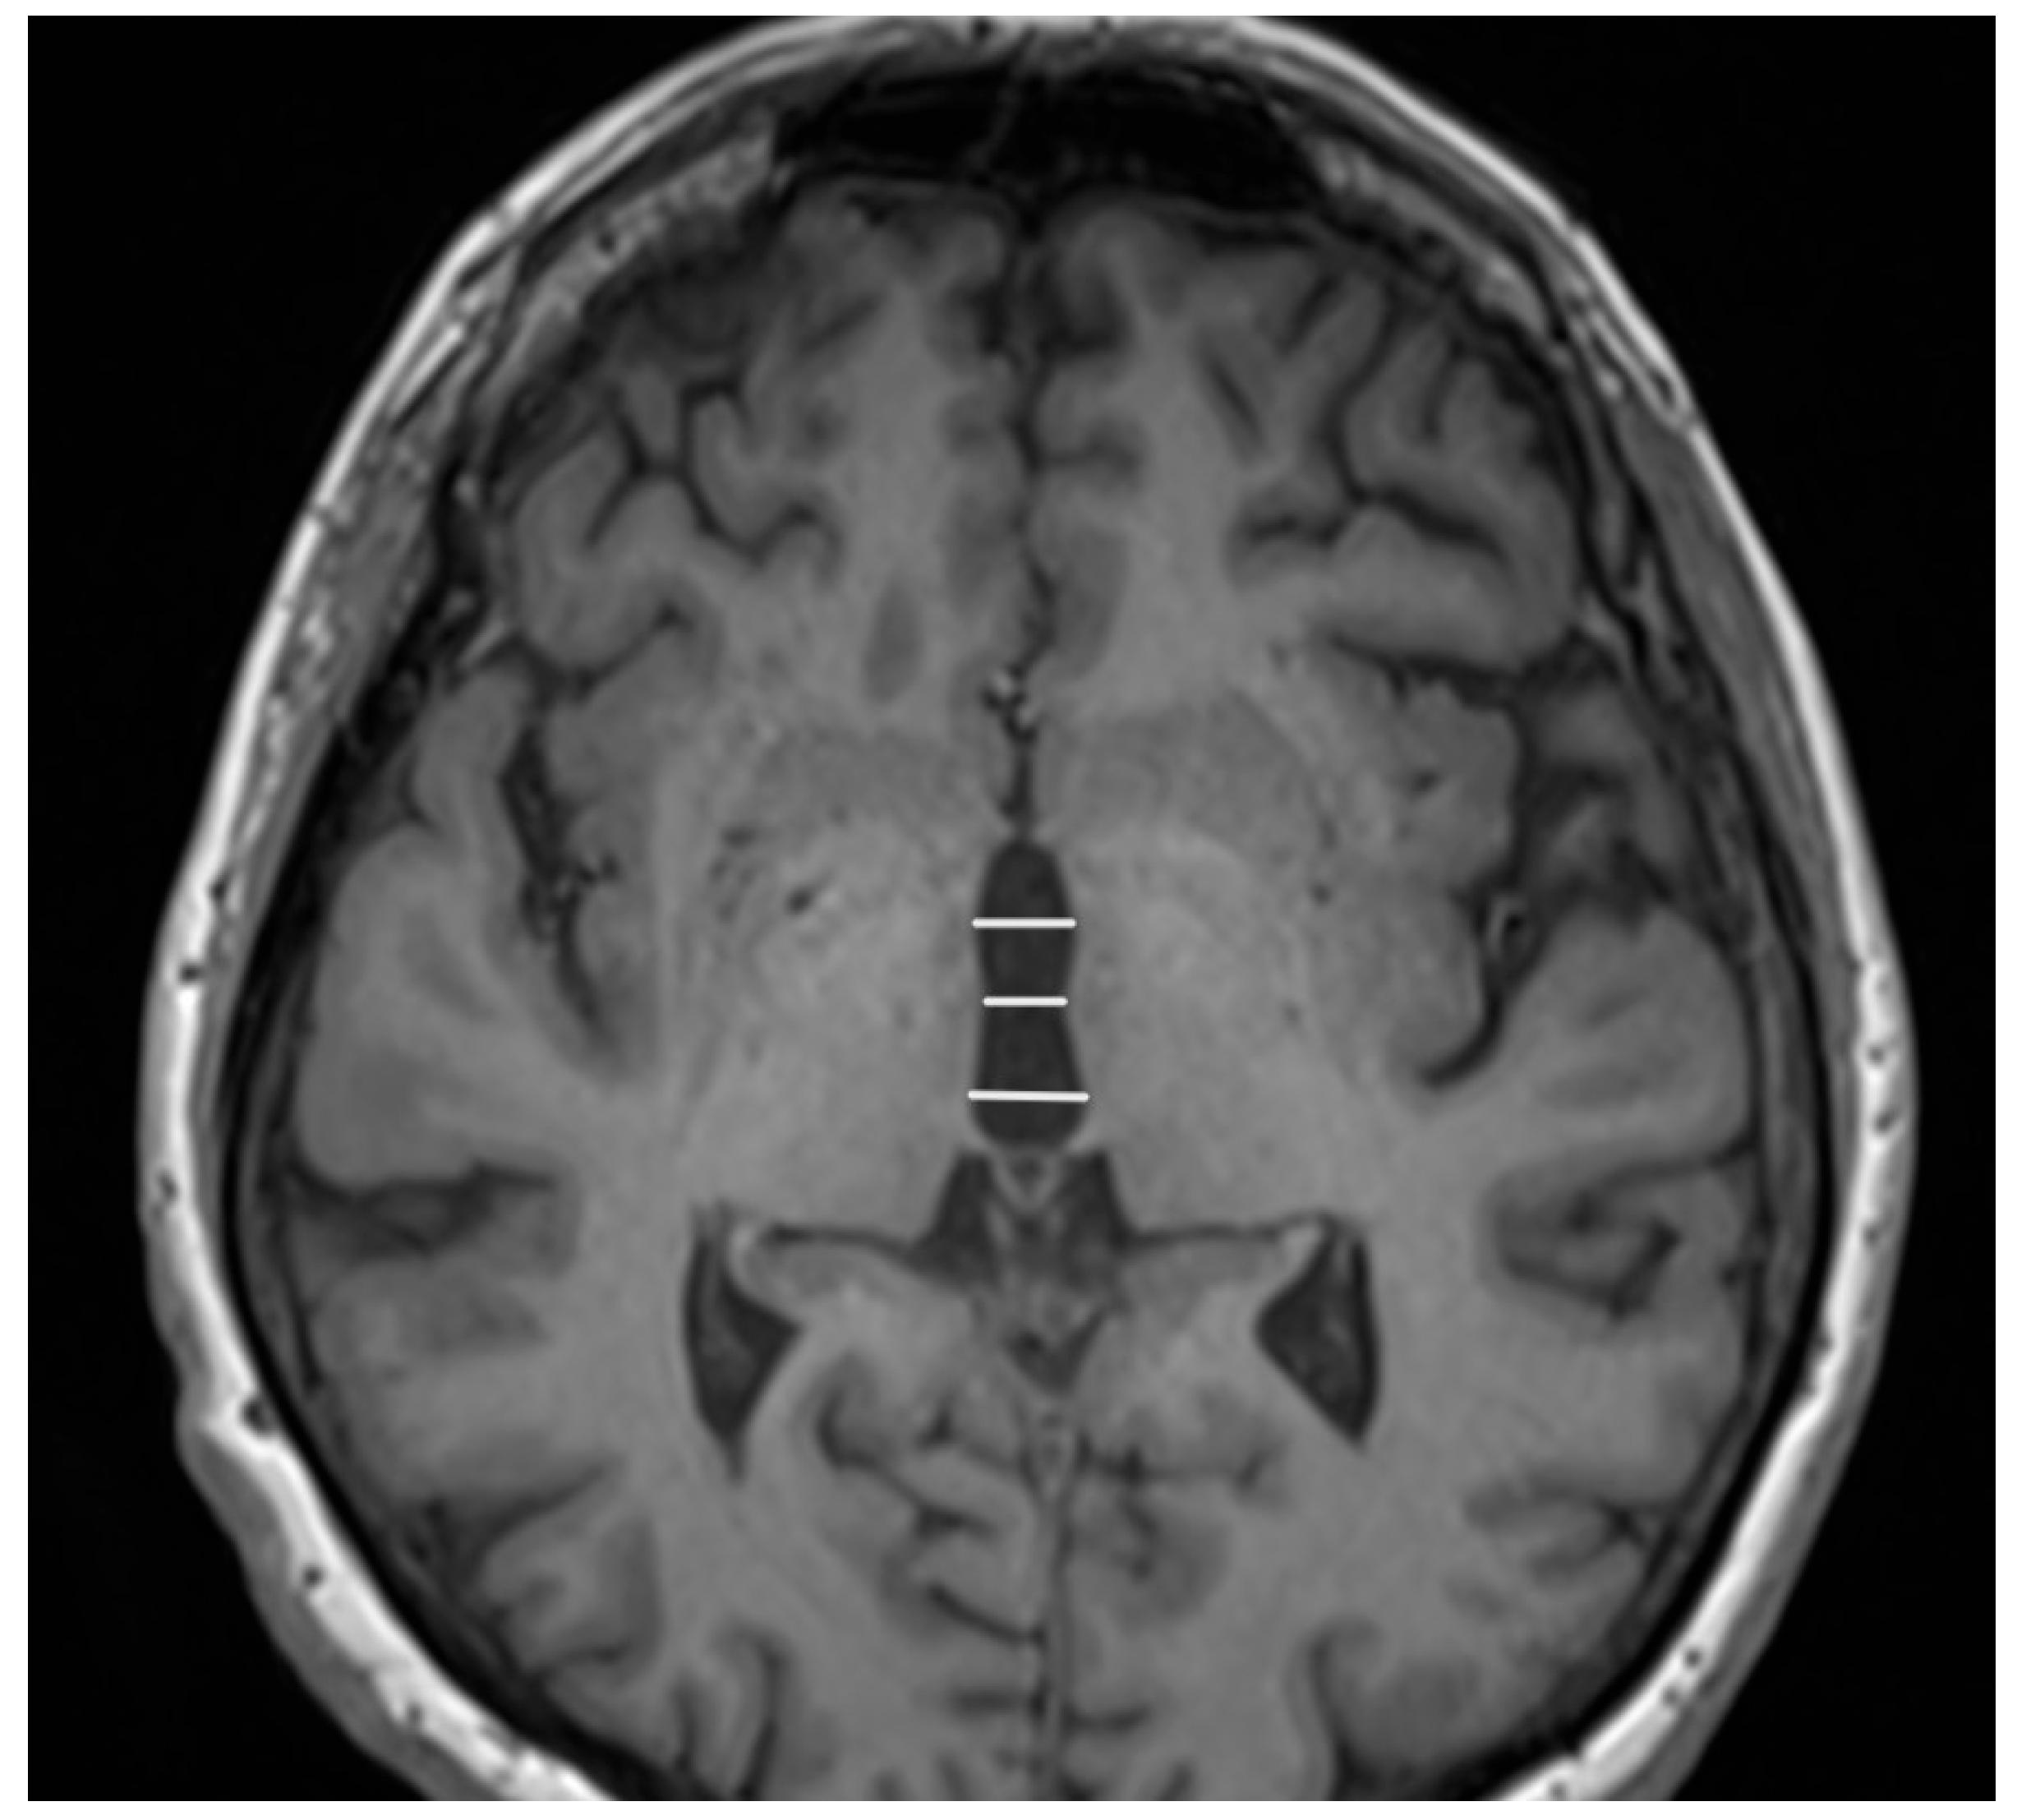

- Quattrone, A.; Morelli, M.; Nigro, S.; Quattrone, A.; Vescio, B.; Arabia, G.; Nicoletti, G.; Nisticò, R.; Salsone, M.; Novellino, F.; et al. A new MR imaging index for differentiation of progressive supranuclear palsy-parkinsonism from Parkinson’s disease. Parkinsonism Relat. Disord. 2018, 54, 3–8. [Google Scholar] [CrossRef]

- Quattrone, A.; Bianco, M.G.; Antonini, A.; Vaillancourt, D.E.; Seppi, K.; Ceravolo, R.; Strafella, A.P.; Tedeschi, G.; Tessitore, A.; Cilia, R.; et al. Development and Validation of Automated Magnetic Resonance Parkinsonism Index 2.0 to Distinguish Progressive Supranuclear Palsy-Parkinsonism from Parkinson’s Disease. Mov. Disord. 2022, 37, 1272–1281. [Google Scholar] [CrossRef]

- Madetko, N.; Alster, P.; Kutyłowski, M.; Migda, B.; Nieciecki, M.; Koziorowski, D.; Królicki, L. Is MRPI 2.0 More Useful than MRPI and M/P Ratio in Differential Diagnosis of PSP-P with Other Atypical Parkinsonisms? J. Clin. Med. 2022, 11, 2701. [Google Scholar] [CrossRef] [PubMed]